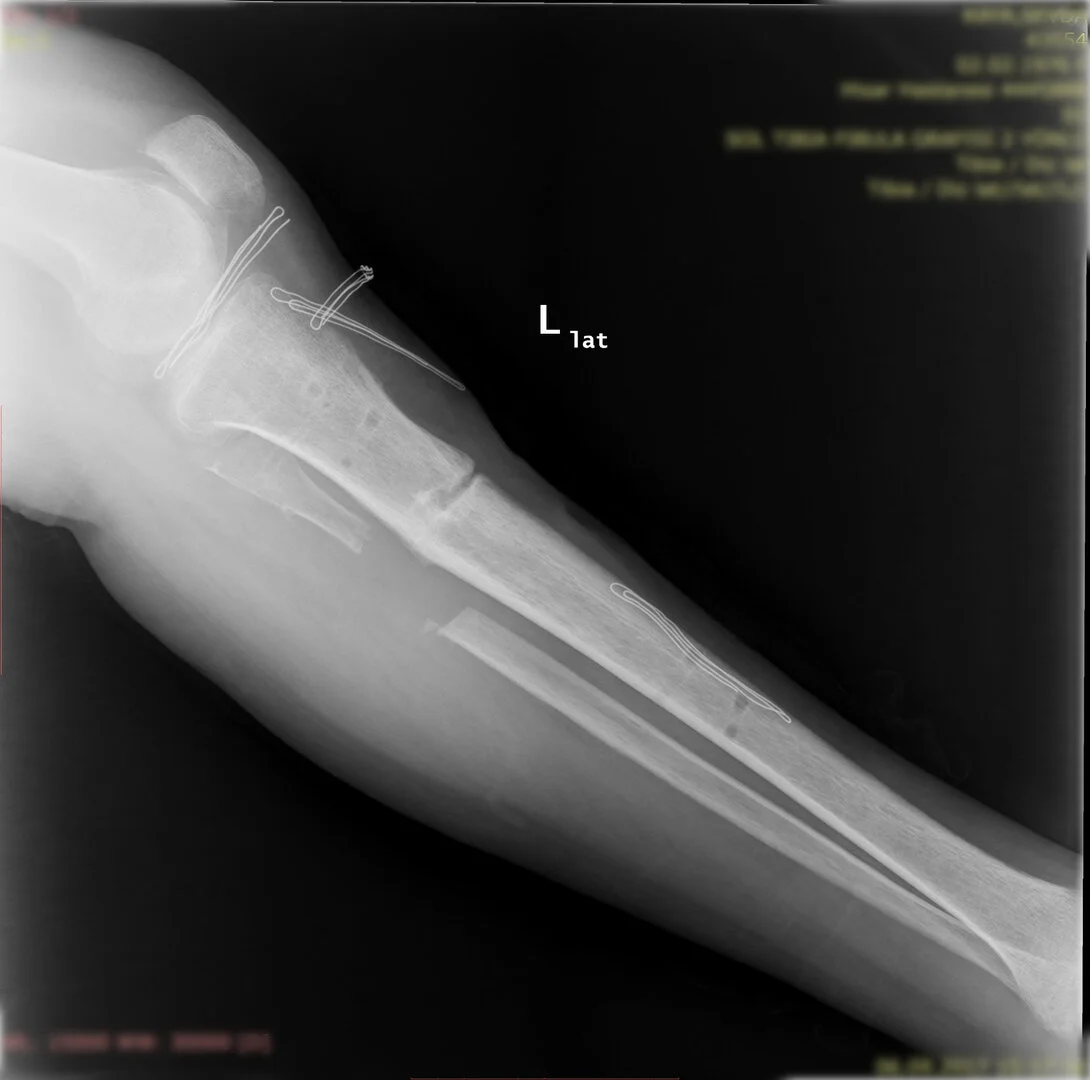

Diğer bir yöntem akut olarak düzeltme yöntemidir. Bu yöntemde kemiğe uygulanılan tespit yöntemi plak-vida kombinasyonu olabileceği gibi bir intramedüller çivi de olabilir.

Görüntüleri büyütmek için üzerine tıklayınız.